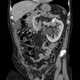

Congenital renal vein thrombosis